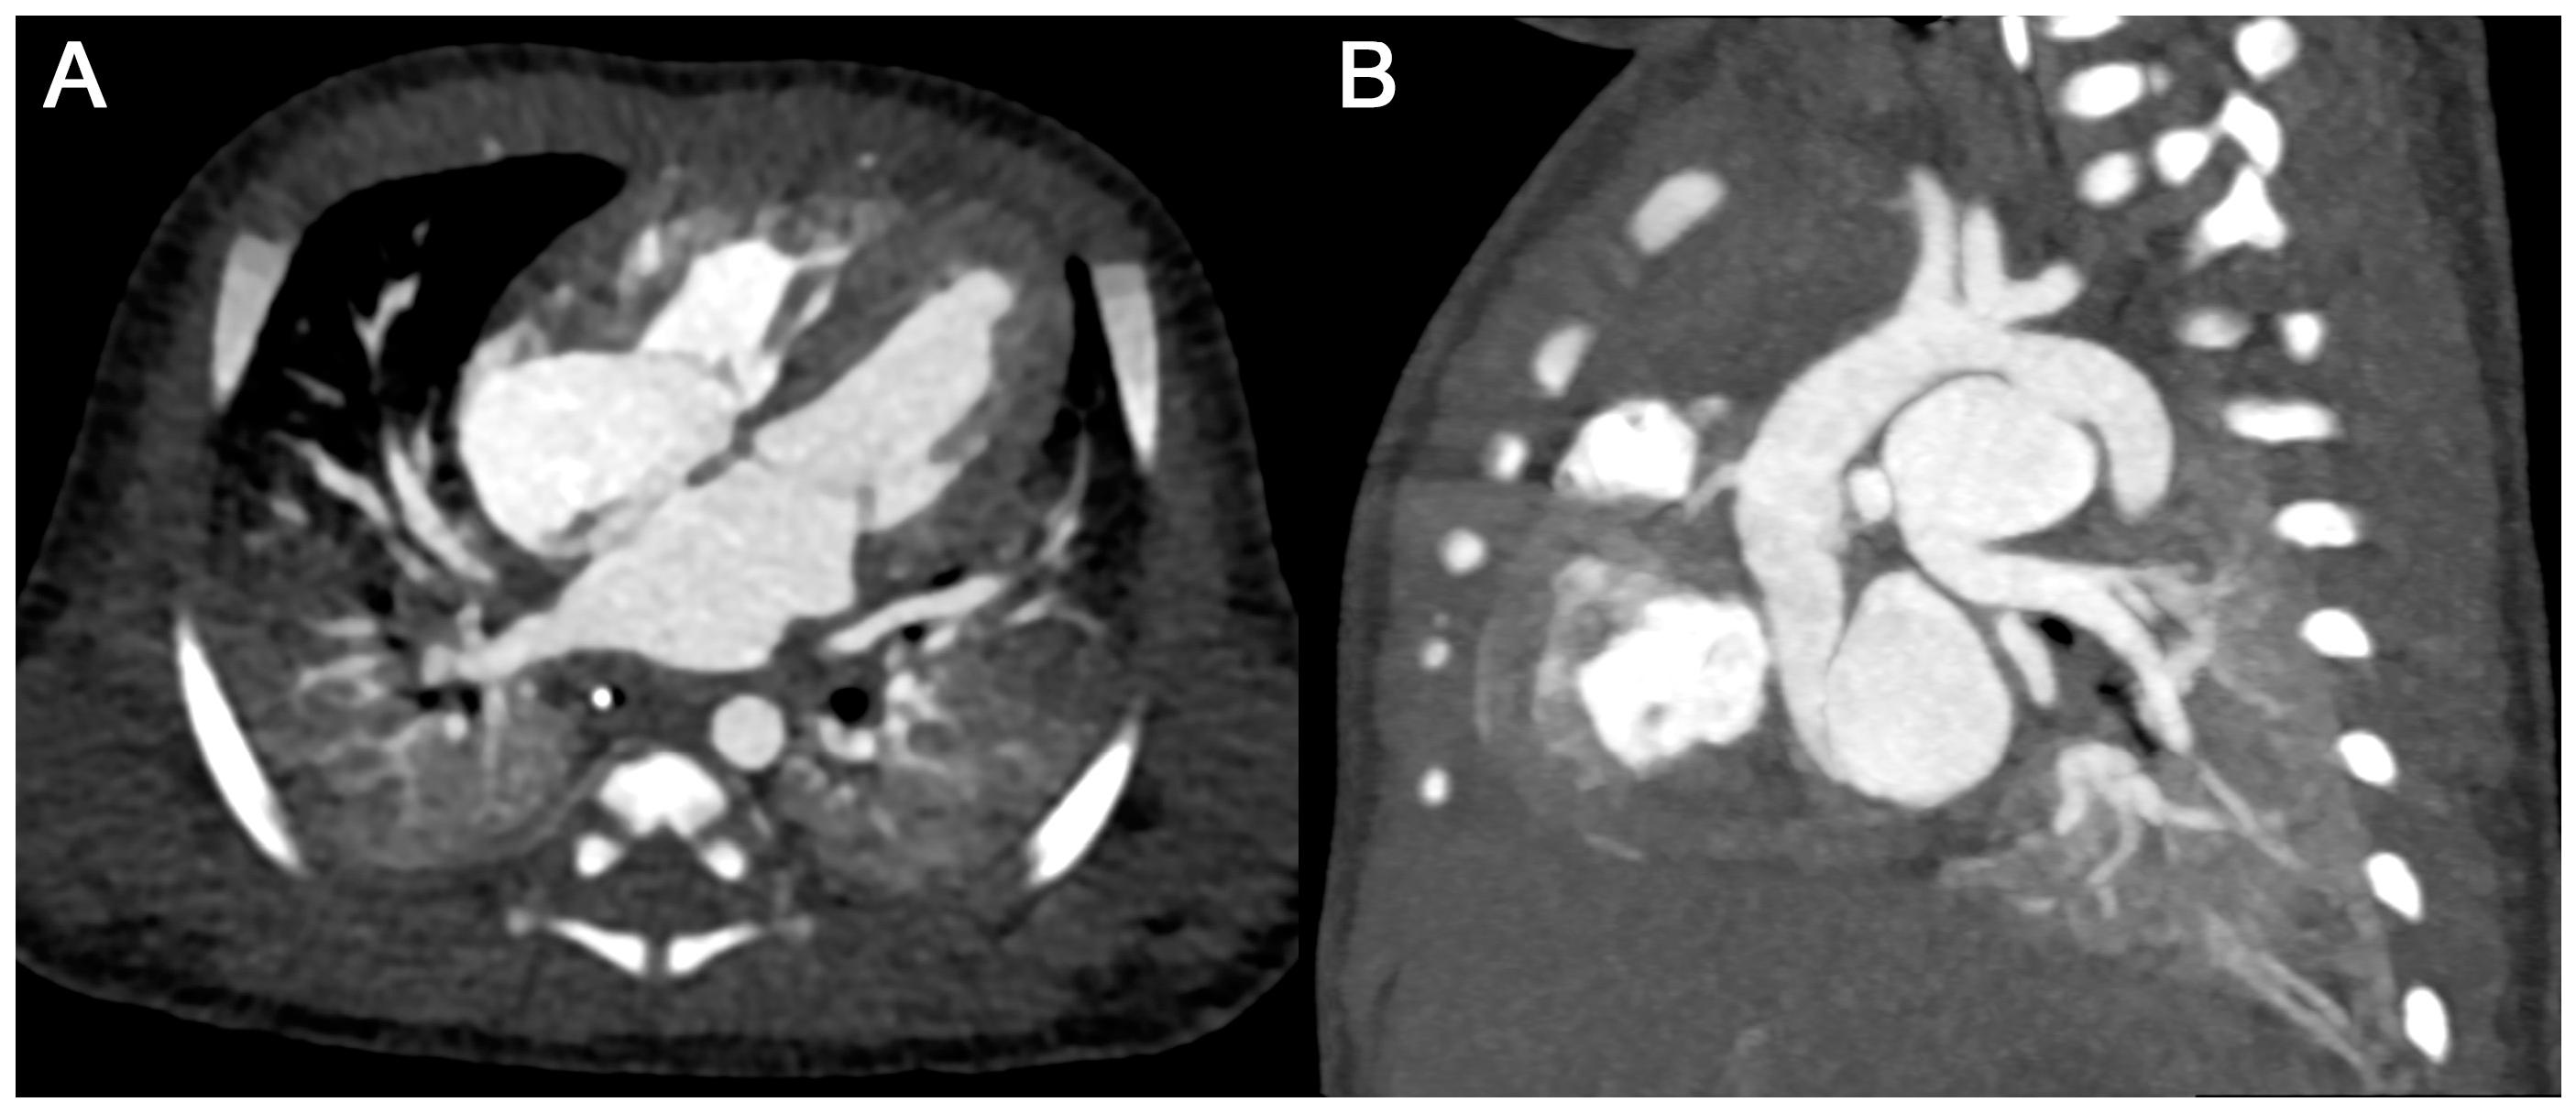

3.3.2. Subjective Image Quality